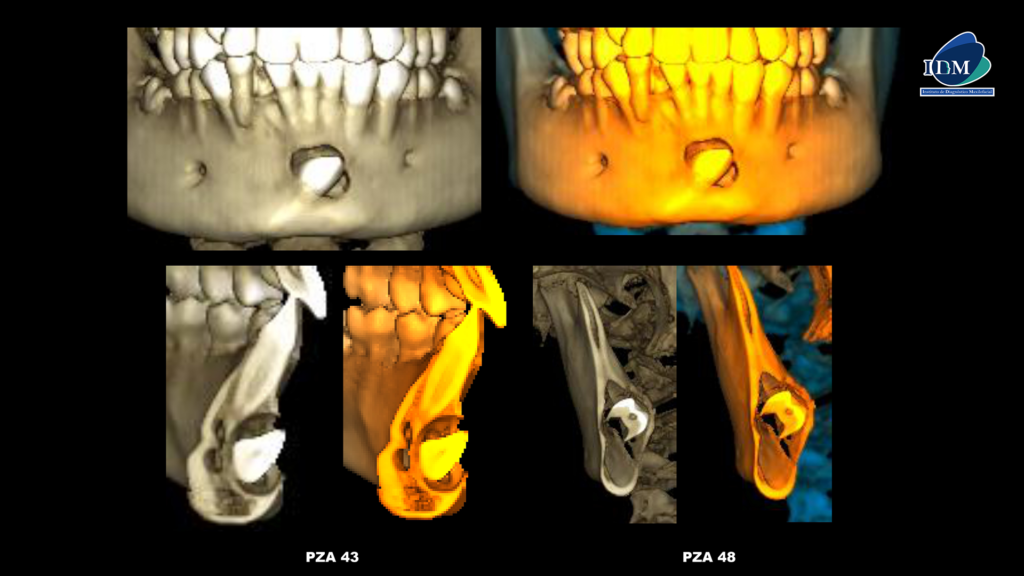

En las reconstrucciones 3D se representa la lesión quística pericoronaria de la pieza 43 y la imagen intracoronaria de la pieza 48 (Figura 4 y 5).

RECONSTRUCCIÓN 3D

- Quiste dentígero asociado a pieza 43. Reabsorción intracoronaria preeruptiva en pieza 48.